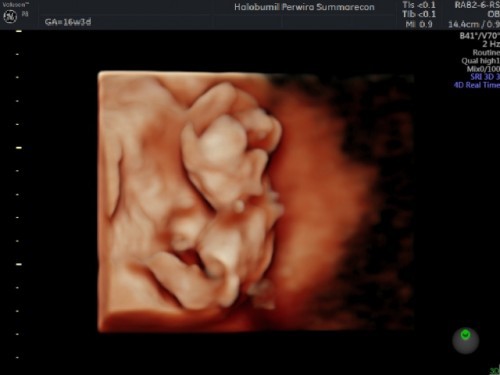

Halo bunda semua.. mau tanya, aku USG 4 weeks tapi kata dokternya masih penebalan rahim, apakah itu normal? Insya Allah besok tanggal 12 maret mau kontrol USG ke 2 di usia 8 weeks.. apakah diusia segitu biasanya udah keliatan janin & djj ya? Selama ini aku ga ngerasain ngeflek, makan apa aja masuk, mual jarang2 banget paling pagi doang itu juga cuma bbrp kali.. ditambah aktifitas yg lumayan, berhubung sama suami sama2 kerja, beda perusahaan, dia kena shift aku non shift jadinya pp naik motor masing2.. pekerjaan rumah pun dibagi 2 jadi aku ttp kerjain kerjaan rumah sebagaimana mestinya. Apa ada yg sama kyk aku? & gimana kondisi kandungannya? Mohon saran & jawabannya ya bund🙏🏻❤️ #ingintahu #pleasehelp #firstbaby #mohonbantu #7week2day #tanyabidan